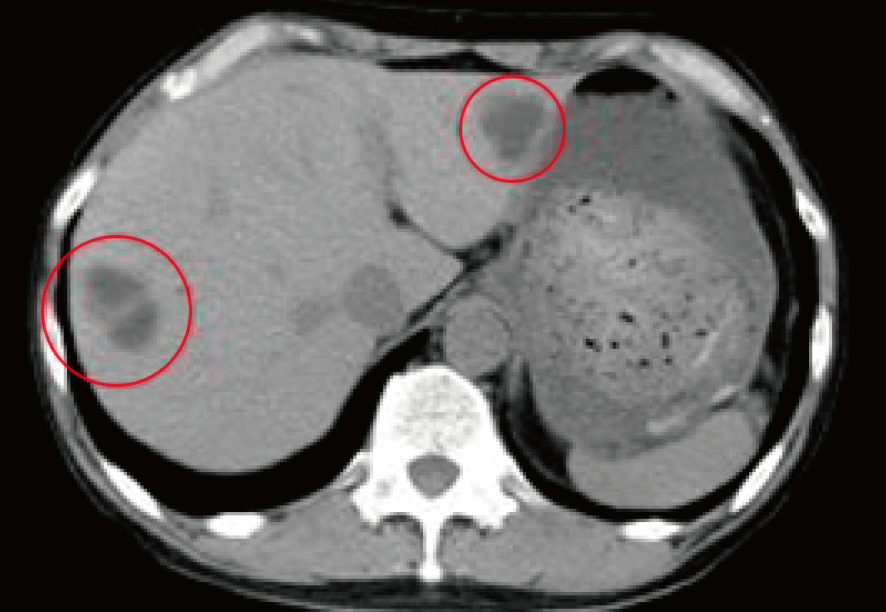

治療前CTでは肝臓の右葉・左葉に存在する肝転移病巣を認めた。

提示したCTは一連の免疫治療・ミトコンドリア治療実施後、およそ6カ月を経過した時点のもの。

画像上、肝臓に多発した転移がんはほぼ消滅し、マーカー値も正常化。

がん腫瘍の消失・共存を目指し引き続き経過観察が必要であると指示。